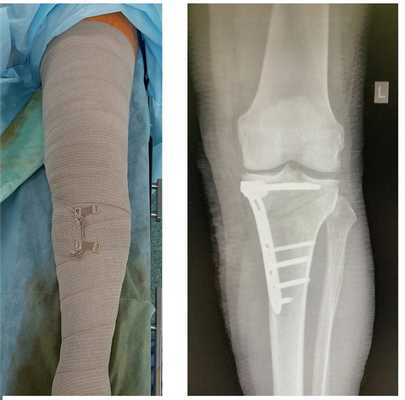

![медиальный артроз коленного сустава, корригирующая остеотомия голени]()

При выполнении «открывающей клин» остеотомии целесообразно использовать аутотрансплантат или аллотрансплантат из губчатой кости для ускорения заживления и сращения остеотомии.

Реабилитационный период длится 6 недель, при этомдозированная нагрузка разрешается сразу же после операции и постепенно увеличивается начиная с 3 недели после вмешательства. Пассивный объём движений можно начинать уже на 2-3 сутки после операции. Рекомендуется стандартный курс антикоагулянтной профилактики на весь период реабилитации.

![лечение артроза коленного сустава, корригирующая остеотомия]()

В результате операции восстанавливается нормальная ось нижней конечности и нагрузка перераспределяется на сохранные наружные отделы сустава. Сразу же после операции видно изменение оси конечности, на рентгенограммах определяется коррекция оси из варуса в небольшой вальгус и хорошо видно как раскрывается разгруженная внутренняя щель коленного сустава.